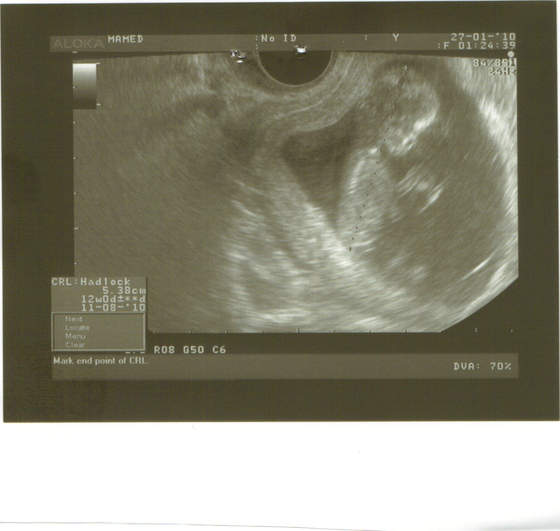

to i ja się pochwalę:

wszystko w jak najlepszym porządku, macha łapkami, kopie nóżkami, a nawet drapie się po głowie. tak sobie myślę, że to już chyba nie fasolka, ale kawał człowieczka